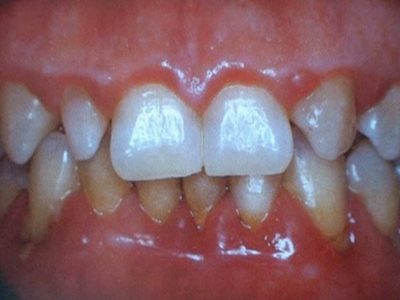

慢性龈炎又称边缘性龈炎或单纯性龈炎,主要表现为游离龈和龈乳头因炎性水肿,而变为鲜红或暗红色,龈缘变厚,龈乳头圆钝肥大。慢性龈炎的患病率高,治愈后仍可复发,部分患者可发展成为牙周炎。

慢性龈炎的病损部位一般局限于游离龈和龈乳头,以前牙区为主,尤其以下前牙区最为显著,患者常因刷牙或咬硬物时牙龈出血而就诊。游离龈和龈乳头颜色变为鲜红或暗红色,病变较重时炎性充血可波及附着龈。龈缘变厚,龈乳头圆钝肥大,可增生呈球状,覆盖牙面。牙龈松软脆弱,缺乏弹性。

对于慢性龈炎,需要通过洁治术彻底清除菌斑和牙石,彻底纠正不良修复体等刺激因素。炎症较重者可配合局部药物治疗,包括过氧化氢溶液、氯己定等。牙龈增生明显,炎症消退后牙龈形态仍不能恢复正常者,可行牙龈成形术。注意定期复查和维护,防止复发。